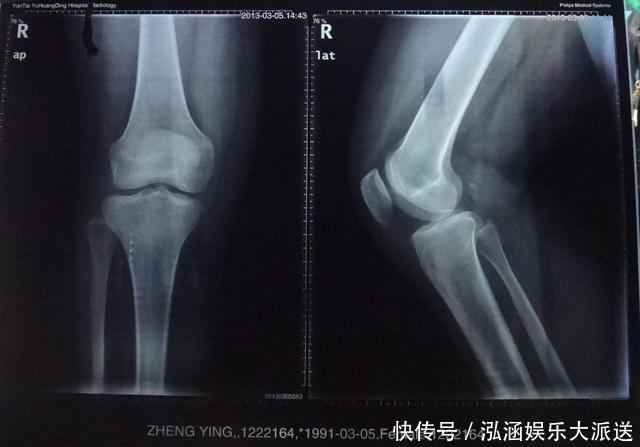

虽然18岁成年了,但是一部分男孩子的骨骼没有完全愈合,还存在长高的空间,所以才会出现前文秦女士的儿子到了22岁还在长高的情形。这是完全正常的,大家不用惊慌。只要弄明白男孩子长高的规律,引导孩子拥有健康的饮食、运动和睡眠,就能充分激发身高潜能,成为运动员或者模特儿指日可待!